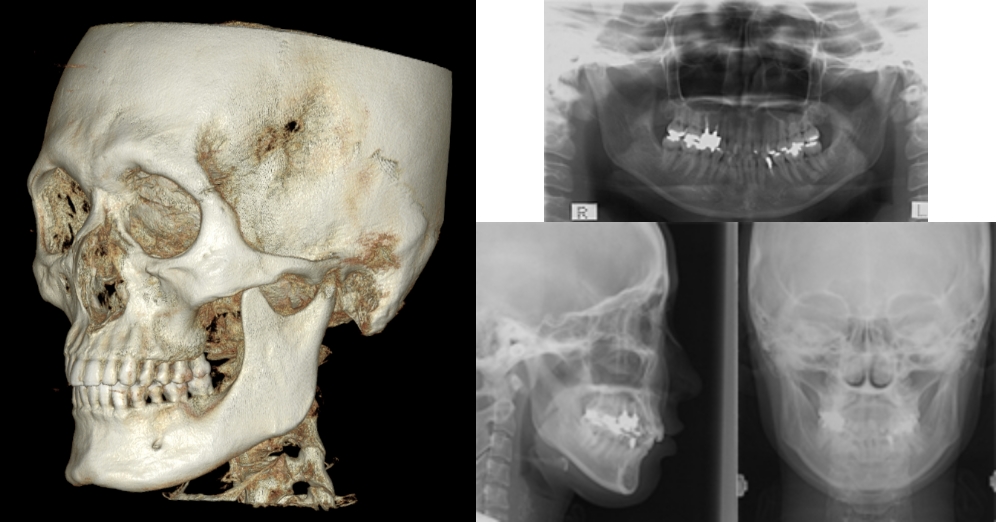

セファロ(頭部X線)分析・3DCT・模型(スキャン)分析を行い、

• 上下顎の骨格バランス

• 歯の角度・上下前後の位置

• 歯列弓の幅・歯ぐきの厚み

• 口元(口唇)の見え方

を総合評価。前歯・奥歯をどこへどれだけ動かすかを設計し、IPR(歯と歯の間をわずかに整える処置)や抜歯の要否、親知らずの扱いまで丁寧に判断します。

レントゲン撮影

模型分析

レントゲン分析

口元のシミュレーション

3Dセットアップで仕上がりを「見える化」

(成人矯正)

当院は自費の成人矯正の全症例で3Dセットアップを行います。

まず、セファロ・3DCT(あごの骨や歯の根の情報)・口腔内スキャン(歯の形とかみ合わせの情報)をとり、これらを重ね合わせて1本ずつ歯をデジタル上で並べ直すシミュレーションを作成します。

何がわかる・何が良い?

• 骨の中で無理のない位置に歯を動かせているかを事前に確認できる

• 歯ぐきの下がりや、骨から外れるなどのリスクを低減できる

• 見た目(口元のバランス)と噛む機能を両立した、現実的で長期安定しやすいゴールを設定できる

• 移動できる範囲(安全域=歯槽骨の包絡)を把握し、過度な移動を避ける設計ができる

当院のこだわり

マウスピース、ワイヤー矯正の双方で「3DCT連動のセットアップ」を採用している医院は、全国でも1割未満です(2025年当院調べ)

当院はこの工程を“当たり前”として、根拠のある計画づくりをしています。

3DCTの治療例